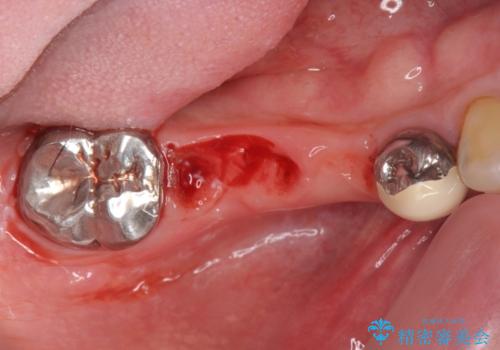

支台を増やし、残った歯の負担を減らし守るために欠損部位にインプラントを埋入し咬合力の負担に対応できる環境を整えます。

インプラント治療は、ブリッジや入れ歯と異なり人口の歯根となるインプラントを顎骨内に埋入することで咬合力に耐える支台を増やせるというメリットがあります。

残った歯の負担を減らすことでより長期的な予後を期待することができます。